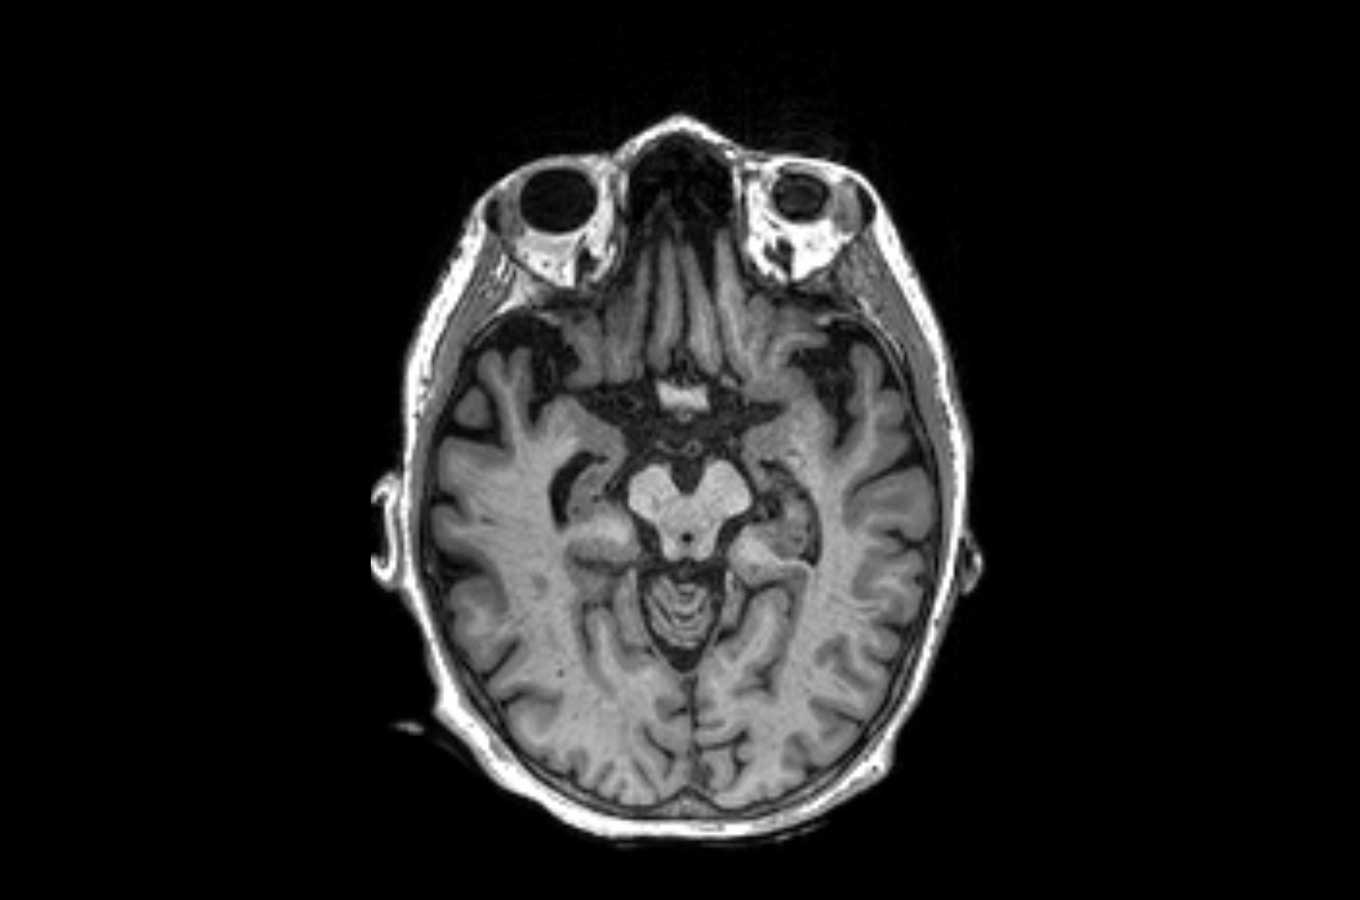

A brain scan showing the presence of progressive supranuclear palsy.

A brain scan showing the presence of progressive supranuclear palsy in the area circled in red. Image by UCSF